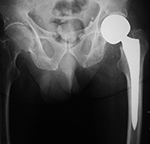

Partial Hip Replacement

There are three basic types of hip arthroplasty. Partial hip replacement or hip hemiarthroplasty replaces the femoral head and neck and leaves intact the native acetabulum. Hip hemiarthroplasty may consist of a single metallic unit, a unipolar hemiarthroplasty or endoprosthesis (figure: hip endoprosthesis). Or it may consist of a bipolar hip hemiarthroplasty in which there is replacement of the femoral head and neck and placement of a prosthetic acetabulum which is press fit into the native acetabulum. The bipolar hip prosthesis acetabulum is a polyethylene lined metal cup. It fits into a small femoral head which is locked to the attached metal femoral stem (Mulcahy, 2012). The bipolar hip hemiarthroplasty allows motion between the prosthetic femoral head and the polyethylene lined cup as well as between the cup and the native acetabulum (figure: bipolar hip prosthesis).

Approximately one-half of hip fractures occur in the femoral neck (intracapsular hip fracture). The unipolar hemiarthroplasty (endoprosthesis) is typically used in

elderly patients with lower life expectancy for

treatment of intracapsular hip fractures. There is removal of the femoral head and placement of a press-fit or cemented

femoral component with a head diameter that

matches that of the acetabulum and articulates

directly with the native acetabular articular cartilage. This is a less traumatic surgery for the patient and enables the patient to have reasonable ambulation quickly after surgery.

| Unipolar hip hemiarthroplasties (endoprostheses) |

Unipolar hip hemiarthroplasty (endoprosthesis) with a cemented femoral component |

Modular non-cemented unipolar hip hemiarthroplasty (endoprosthesis) |

| These are single piece prostheses press fit into the native acetabulum and the native femur. From Benjamin, 1994 |

Note the collar abutting the femoral calcar. From Benjamin, 1994 |

Note the collar abutting the femoral calcar. |